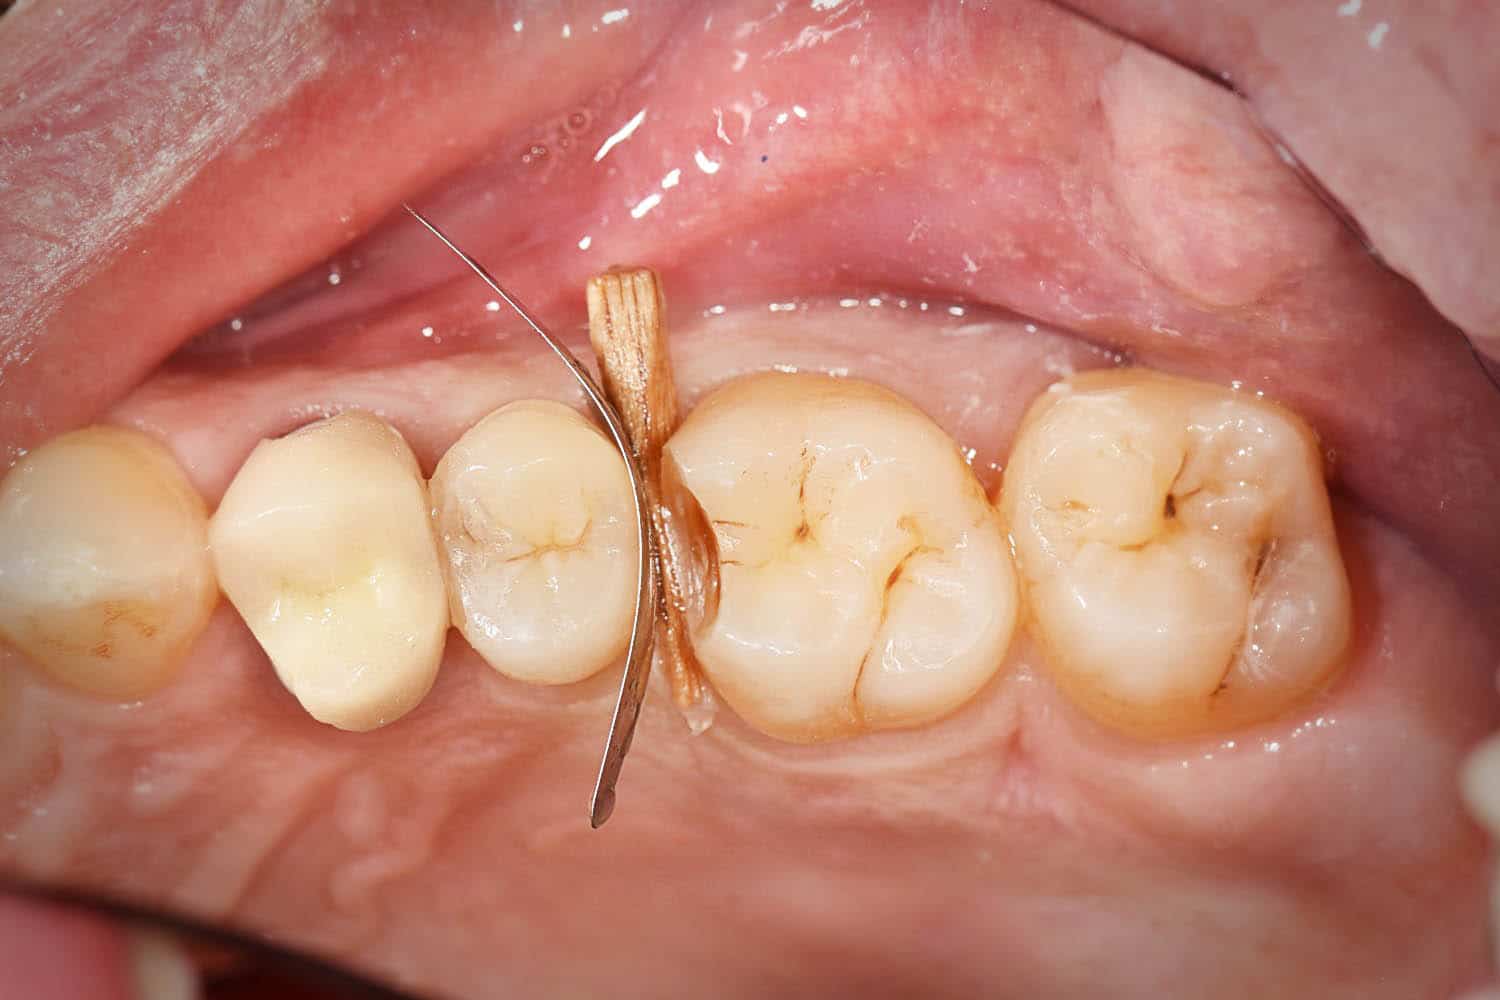

Excellent protection of adjacent teeth during preparation (sandblasting, etching, drilling)